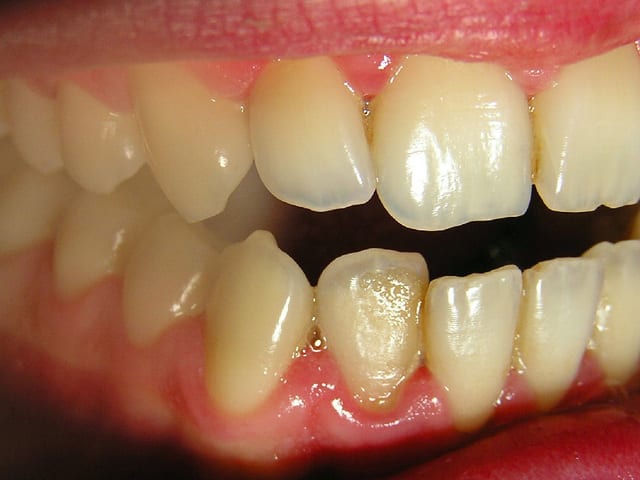

...Et les photos prises aujourd'hui, juste avant la séance de démonstration du contrôle de plaque.

Je n'ai pas fait de microscope durant cette séance car on sort tout juste du traitement antibiotique et ça n'aurait certainement pas montré grand chose.

Le but est de le revoir dans un mois pour déterminer sa motivation et son efficacité en matière de contrôle de plaque. Et pour voir comment la flore recolonise le terrain avant de lithotritier.